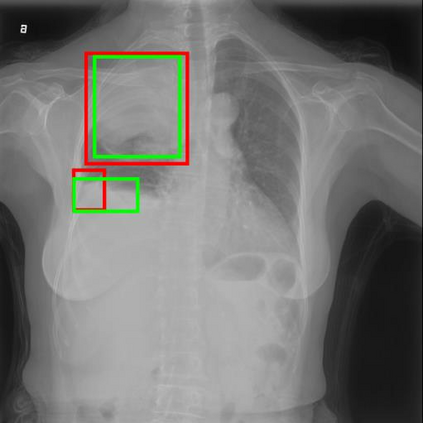

Chest X-ray (CXR) is the most typical diagnostic X-ray examination for screening various thoracic diseases. Automatically localizing lesions from CXR is promising for alleviating radiologists' reading burden. However, CXR datasets are often with massive image-level annotations and scarce lesion-level annotations, and more often, without annotations. Thus far, unifying different supervision granularities to develop thoracic disease detection algorithms has not been comprehensively addressed. In this paper, we present OXnet, the first deep omni-supervised thoracic disease detection network to our best knowledge that uses as much available supervision as possible for CXR diagnosis. We first introduce supervised learning via a one-stage detection model. Then, we inject a global classification head to the detection model and propose dual attention alignment to guide the global gradient to the local detection branch, which enables learning lesion detection from image-level annotations. We also impose intra-class compactness and inter-class separability with global prototype alignment to further enhance the global information learning. Moreover, we leverage a soft focal loss to distill the soft pseudo-labels of unlabeled data generated by a teacher model. Extensive experiments on a large-scale chest X-ray dataset show the proposed OXnet outperforms competitive methods with significant margins. Further, we investigate omni-supervision under various annotation granularities and corroborate OXnet is a promising choice to mitigate the plight of annotation shortage for medical image diagnosis.